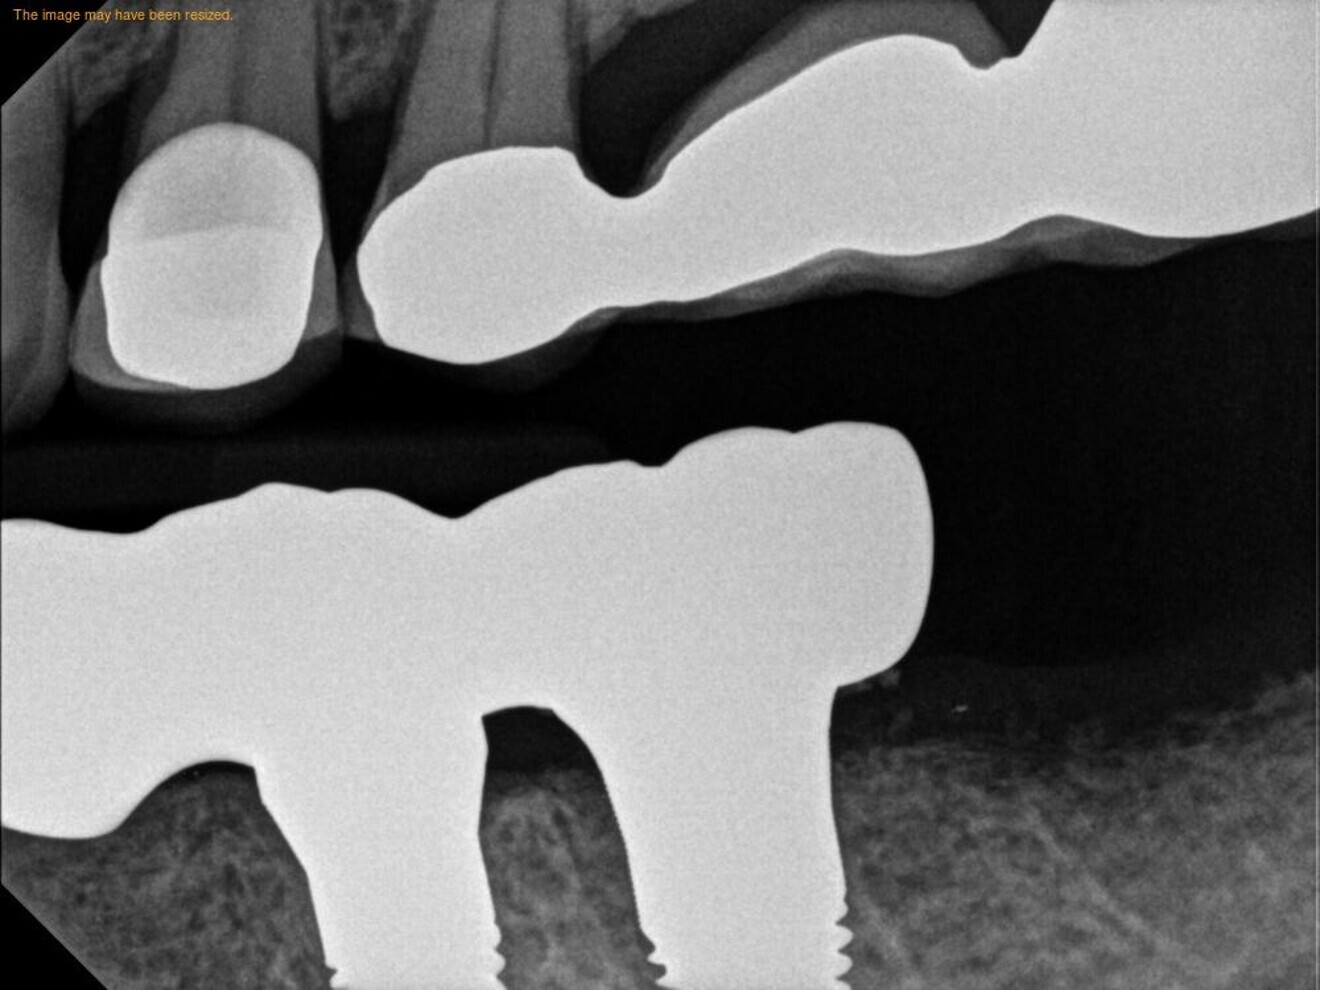

Figs. 17a–c: Final radiographs showing the bone levels and final restoration.

A final full-arch zirconia restoration was manufactured, and the final seating was verified with radiographs (Fig. 17) and cemented with PANAVIA SA Cement Universal (Kuraray Noritake Dental). The patient returned two weeks later for an occlusion check and adjustment along with an oral hygiene check. Pink firm gingiva around all the implants was noted such that it was even difficult to get a probe into the sulcus (Fig. 18).